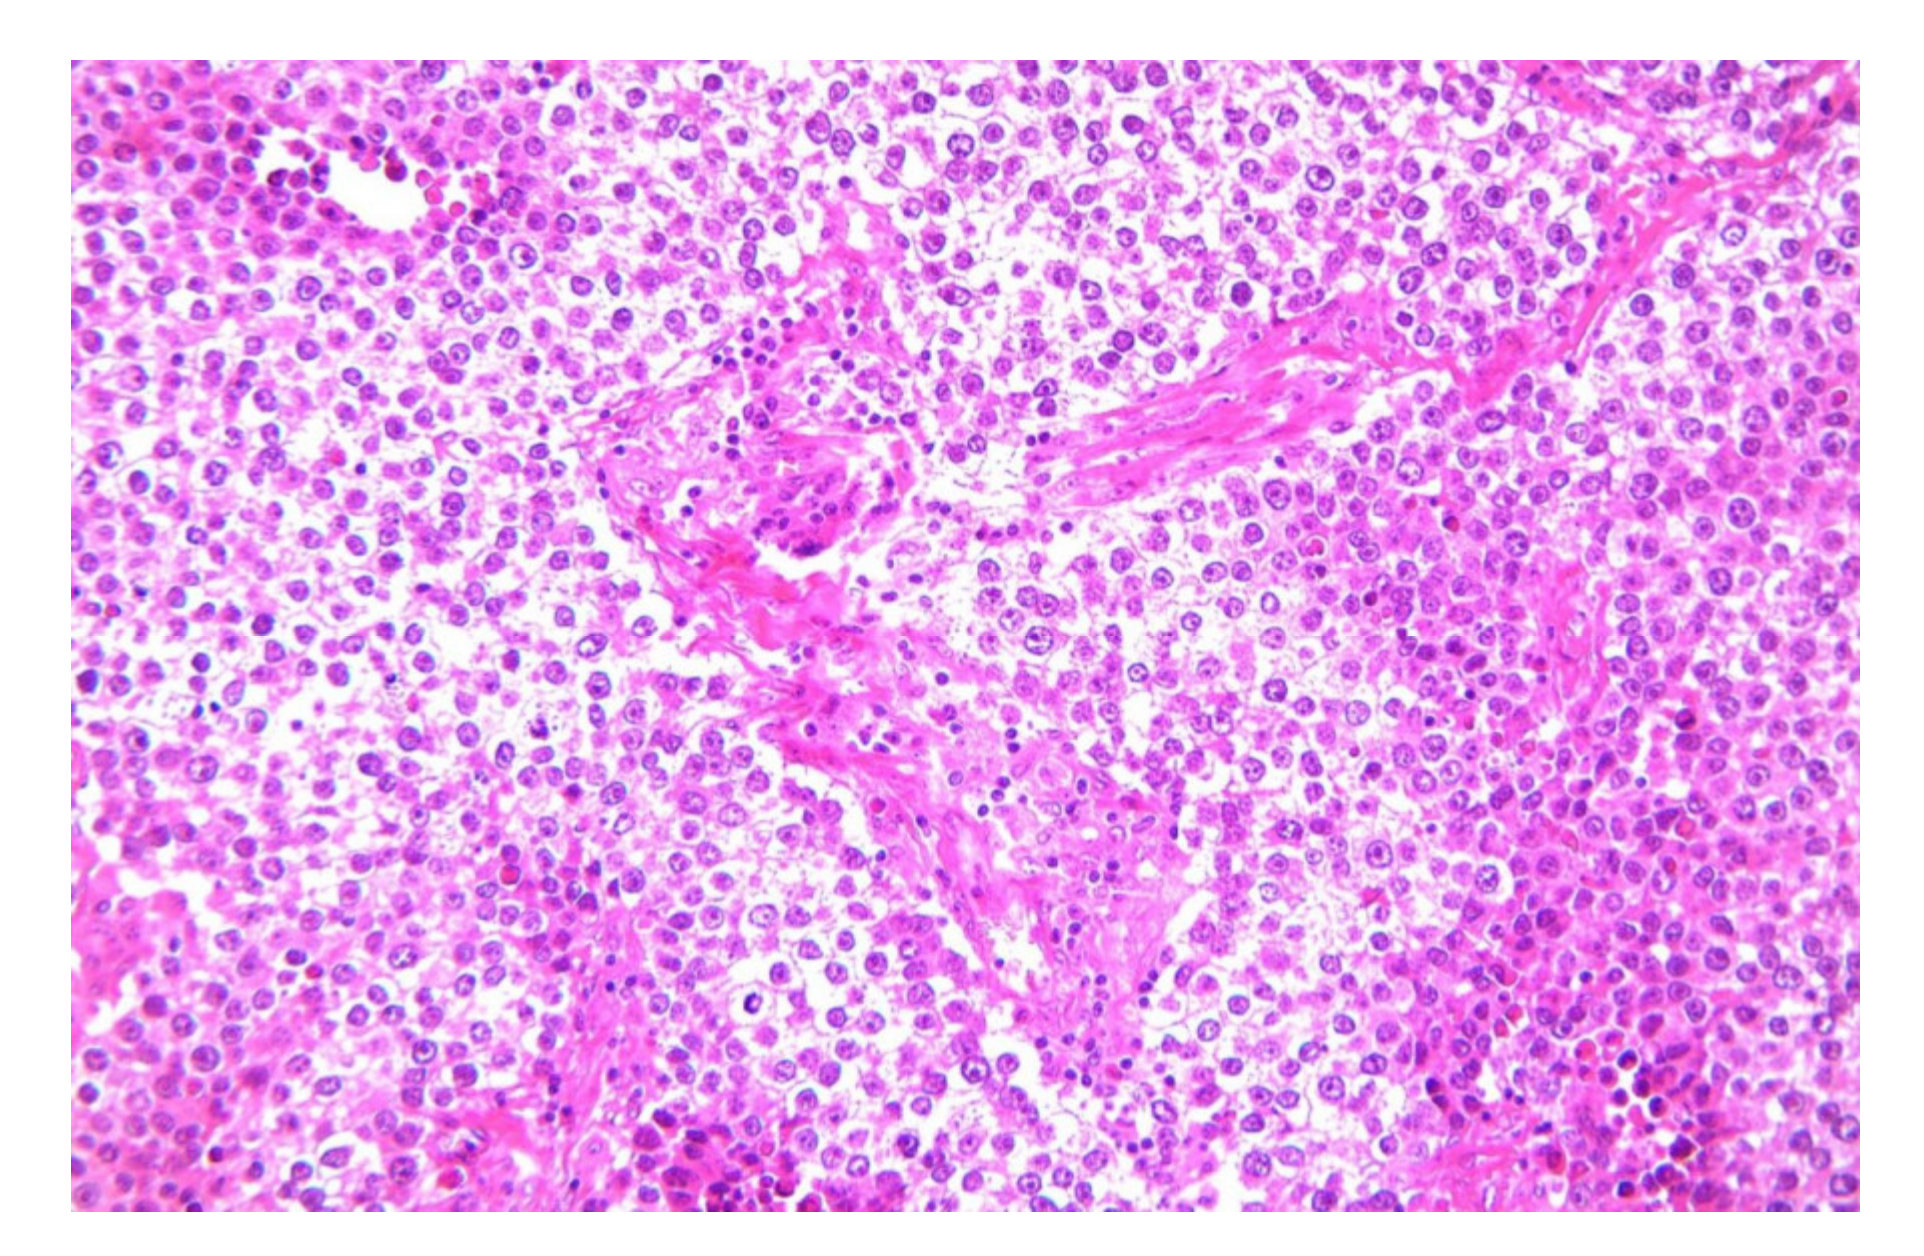

2.1. Dysgerminoma

2.1.2. Microscopic Features